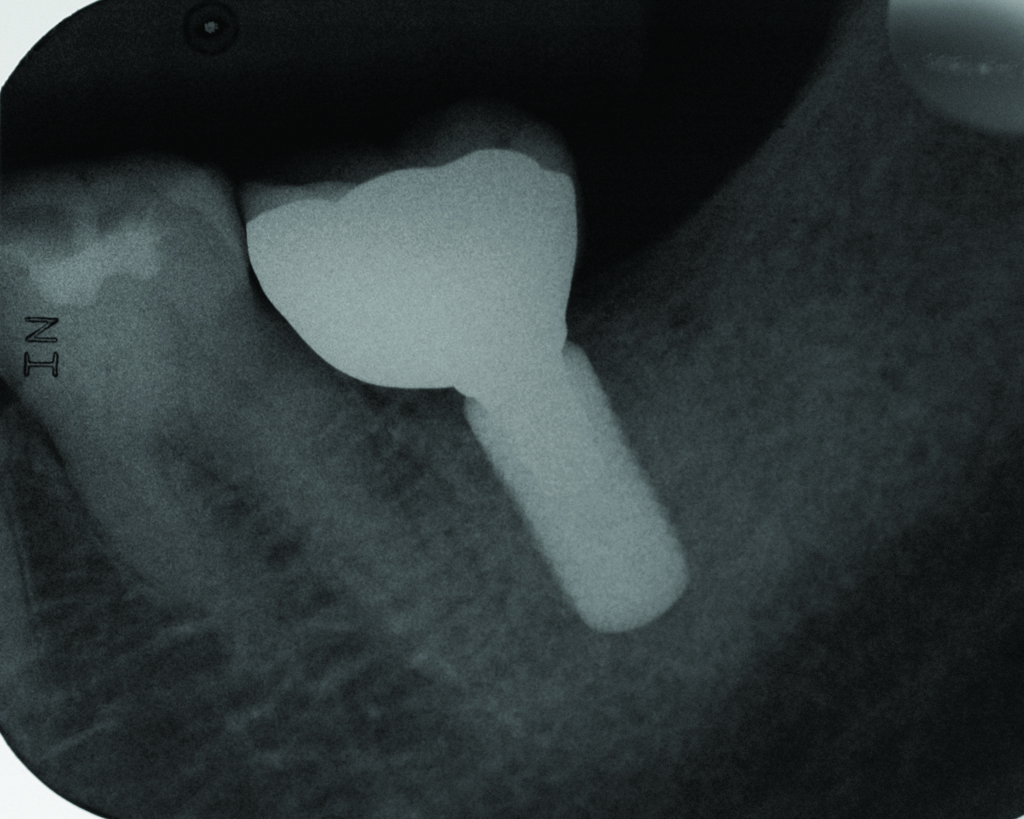

Peri-implant diseases present in two forms—peri-implant mucositis (Figure 1 and Figure 2) and peri-implantitis (Figure 3 and Figure 4). Both involve an inflammatory reaction in the tissues surrounding an implant—ie, bleeding on probing and/or suppuration; probing depths usually exceed 4 mm.1,3 However, when there is also bone loss present beyond the physiologic remodeling that may occur after implant placement, a diagnosis of peri-implantitis should be made, as this condition, when compared to mucositis, is far more serious and difficult to resolve.4

Radiograph of the area suggests moderate to advanced bone loss at the mesial aspect making the diagnosis peri-implantitis.

Figure 4